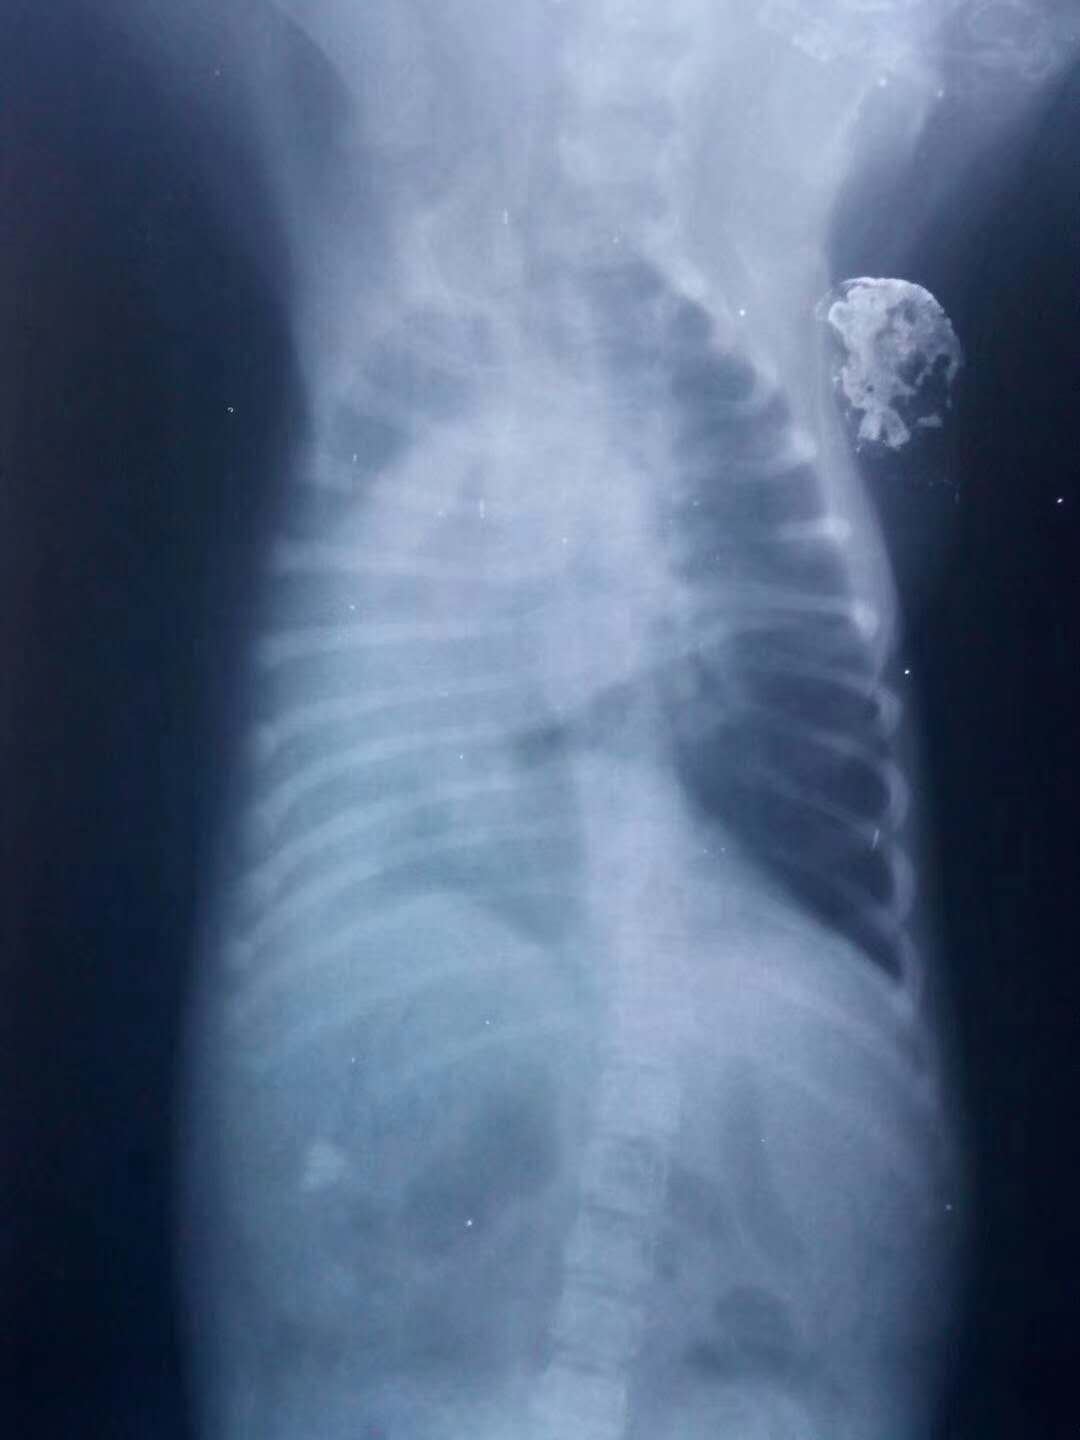

CPV/犬細(xì)小+肺炎/大葉性肺炎病例出院: 熊版阿拉,2個月左右,疫苗還未做

來時: 無食欲,高燒,咳頻繁,有喘,精神萎靡,后出現(xiàn)鐵銹色鼻液..... 經(jīng)相關(guān)化驗(yàn),拍x片,確診為:CPV/犬細(xì)小病毒+大葉性肺炎 ,住院治療數(shù)天,狀態(tài)逐步恢復(fù)正常, 今兒出院  。